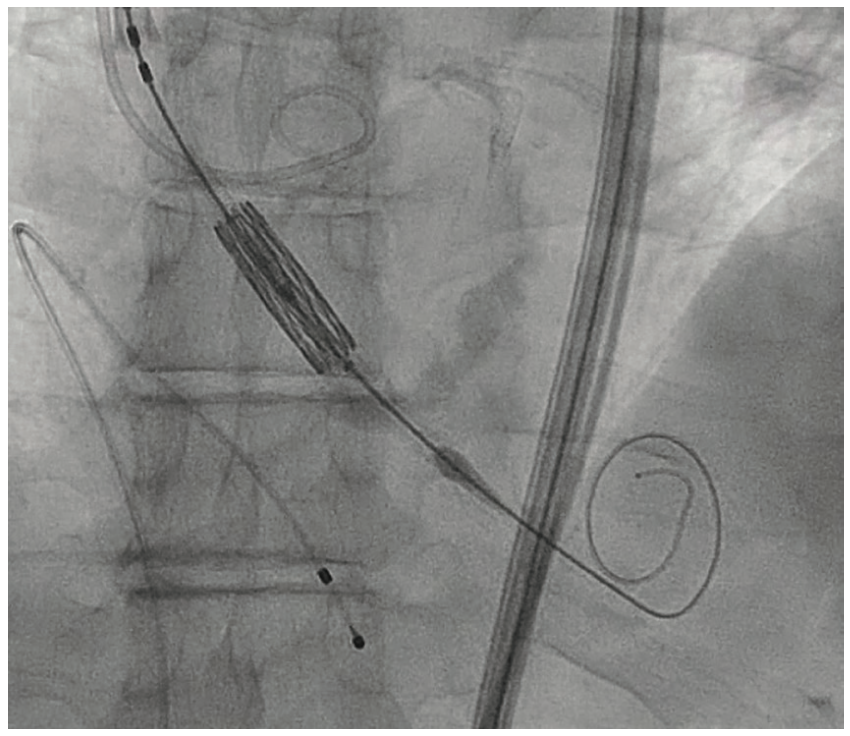

During the TAVR procedure, a Sapien 3 26 mm valve was loaded over a Safari wire (Boston Scientific) and advanced into the aortic annulus under fluoroscopy, with good planar angle positioning confirmed using contrast injection. After valve placement, rapid ventricular pacing was performed and the valve was deployed. However, immediately following deployment, the valve embolized into the ascending aorta. The valve was carefully pulled distally and secured just proximal to the origin of the right brachiocephalic artery. It was dilated with an extra 4 mL volume with two inflations performed. To confirm the patency of the right subclavian artery and the right brachiocephalic artery, access was subsequently obtained in the right radial artery, and no difference in the arterial pressure was noted as the catheter was advanced from the right radial artery into the aortic root. A second Sapien 3 26 mm valve was then loaded over the Safari wire and was similarly advanced into the aortic annulus under fluoroscopy, with good coplanar angle positioning confirmation via contrast injection. After rapid ventricular pacing, the second valve was deployed without issue. A post procedure aortogram confirmed good valve positioning, the absence of significant paravalvular leak, and patency of the left coronary artery. A limited echocardiogram also confirmed good valve positioning, the absence of paravalvular leak, and the absence of pericardial effusion. The patient tolerated the procedure well and left the cardiac catheterization laboratory in a stable condition. After chest x-ray confirmed stable positioning of the embolized valve in the ascending aorta, the patient was discharged on postoperative day one with a scheduled follow-up visit in three weeks.